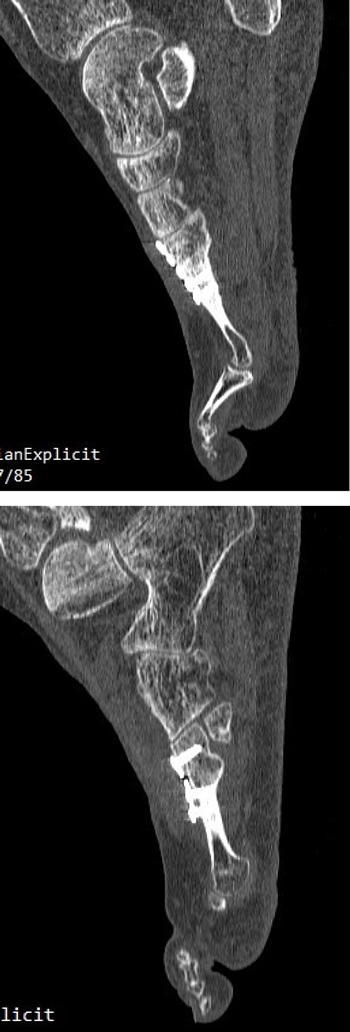

Se realizó radiografía dorso-plantar en carga del pie derecho (Figura 1) que mostraba una imagen radiológica compatible con ausencia de consolidación de las osteotomías en las bases de 2.º, 3.º y 4.º metatarsianos, además de la presencia de hallux abductus valgus. Se solicitó una tomografía axial computarizada (TAC) para estudiar más detenidamente el estado actual del proceso de consolidación ósea. La paciente acudió con resultado de TAC el 5 de mayo de 2015, donde se evidenció la ausencia completa de consolidación ósea en segundo metatarsiano (Figuras 2A y 2B), consolidación prácticamente completa de tercer metatarsiano (Figura 2C) y la presencia de callo óseo con consolidación incompleta en el cuatro metatarsiano (Figura 2D).

Figura 1. Radiografía dorso-plantar en carga del pie derecho. Se evidencia la ausencia de consolidación de las osteotomías en las bases de 2.º, 3.º y 4.º metatarsianos después de 9 meses de la intervención inicial.

Figura 2. Radiografía dorso-plantar en carga del pie derecho. Se evidencia la ausencia de consolidación de las osteotomías en las bases de 2.º, 3.º y 4.º metatarsianos después de 9 meses de la intervención inicial.